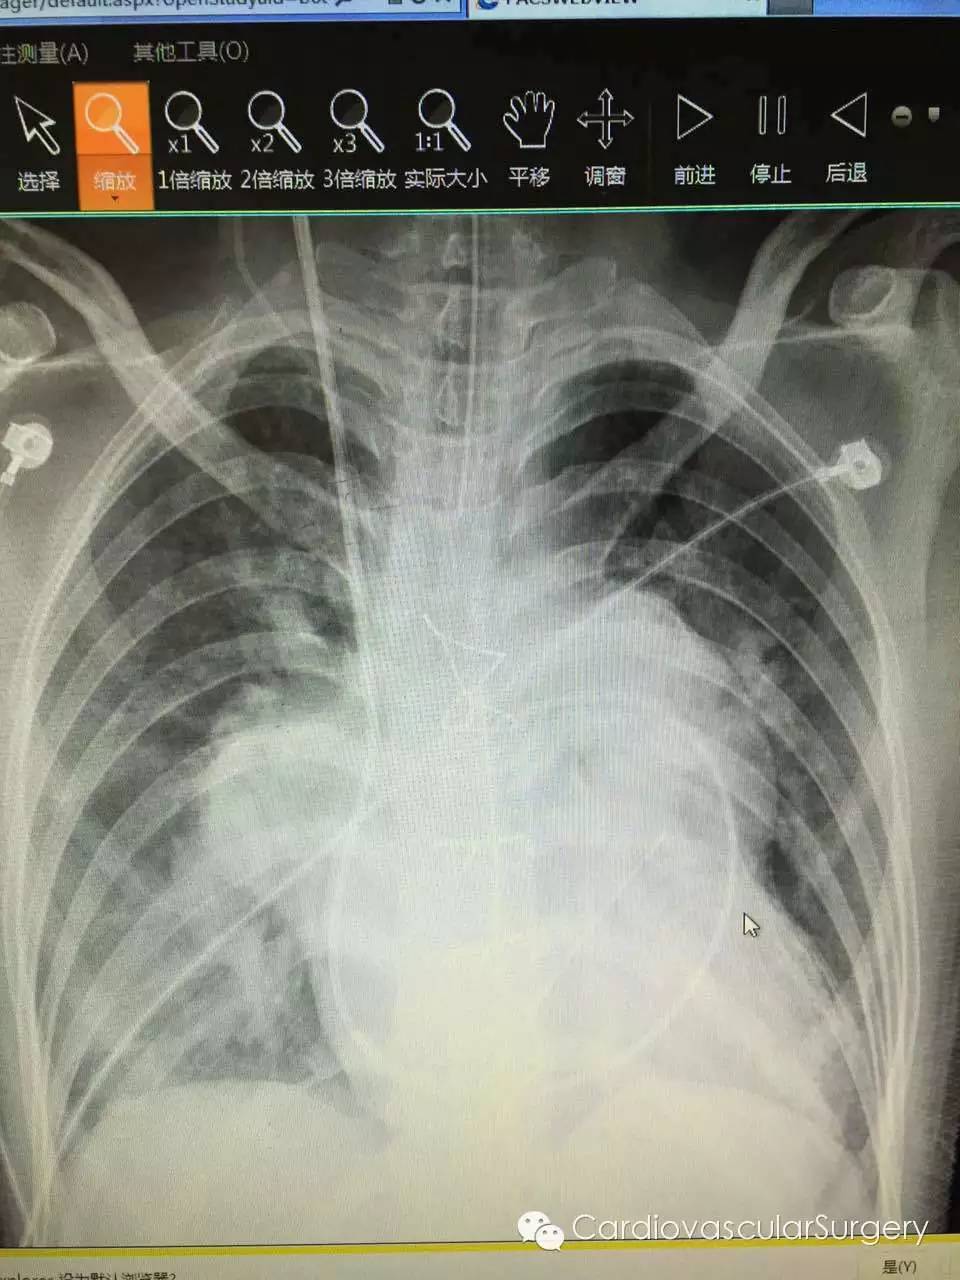

房间隔缺损, 右房右室大, 肺充血